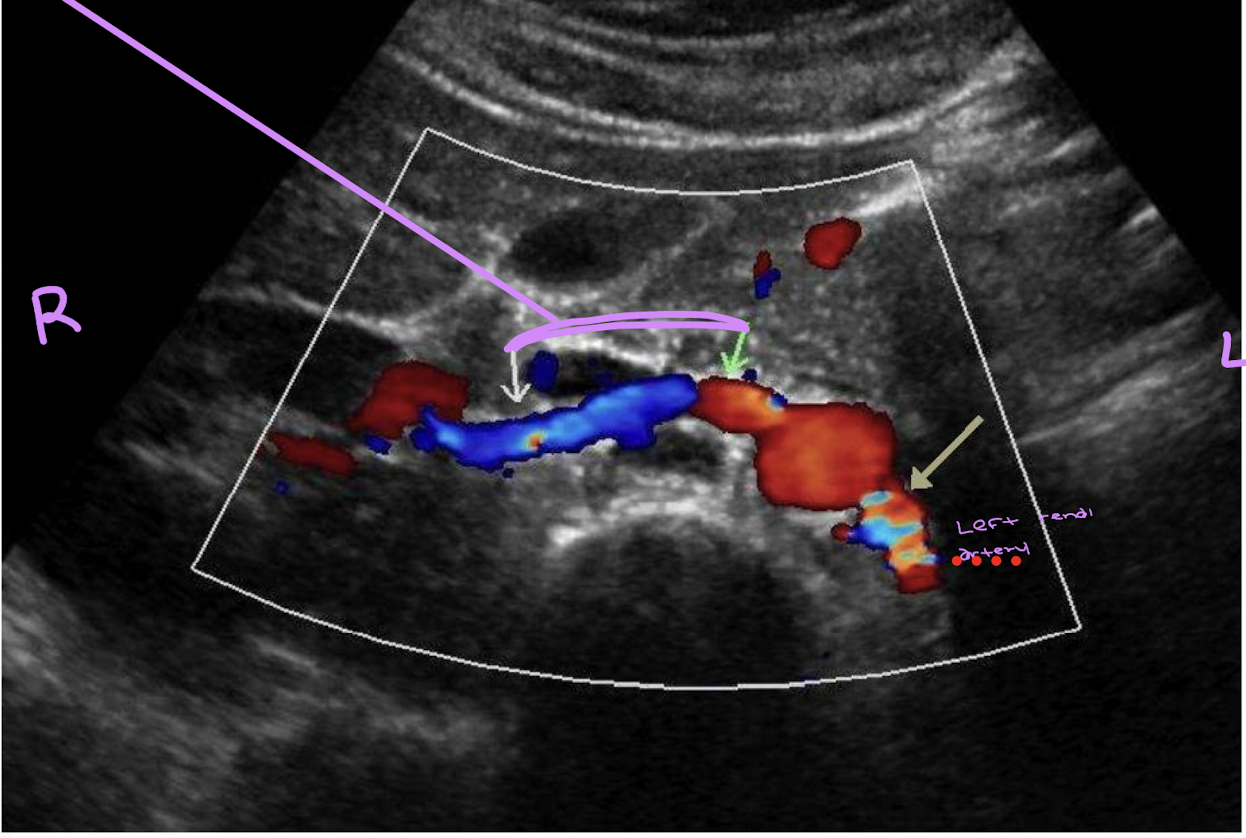

This is right coronal view of the proximal renal arteries. Identify if the right or left arteries are on the orange or blue.

Orange: left

blue: right (posterior to the IVC)

keep in mind the right renal artery is positioned at 10:00 and the left is at 4:00